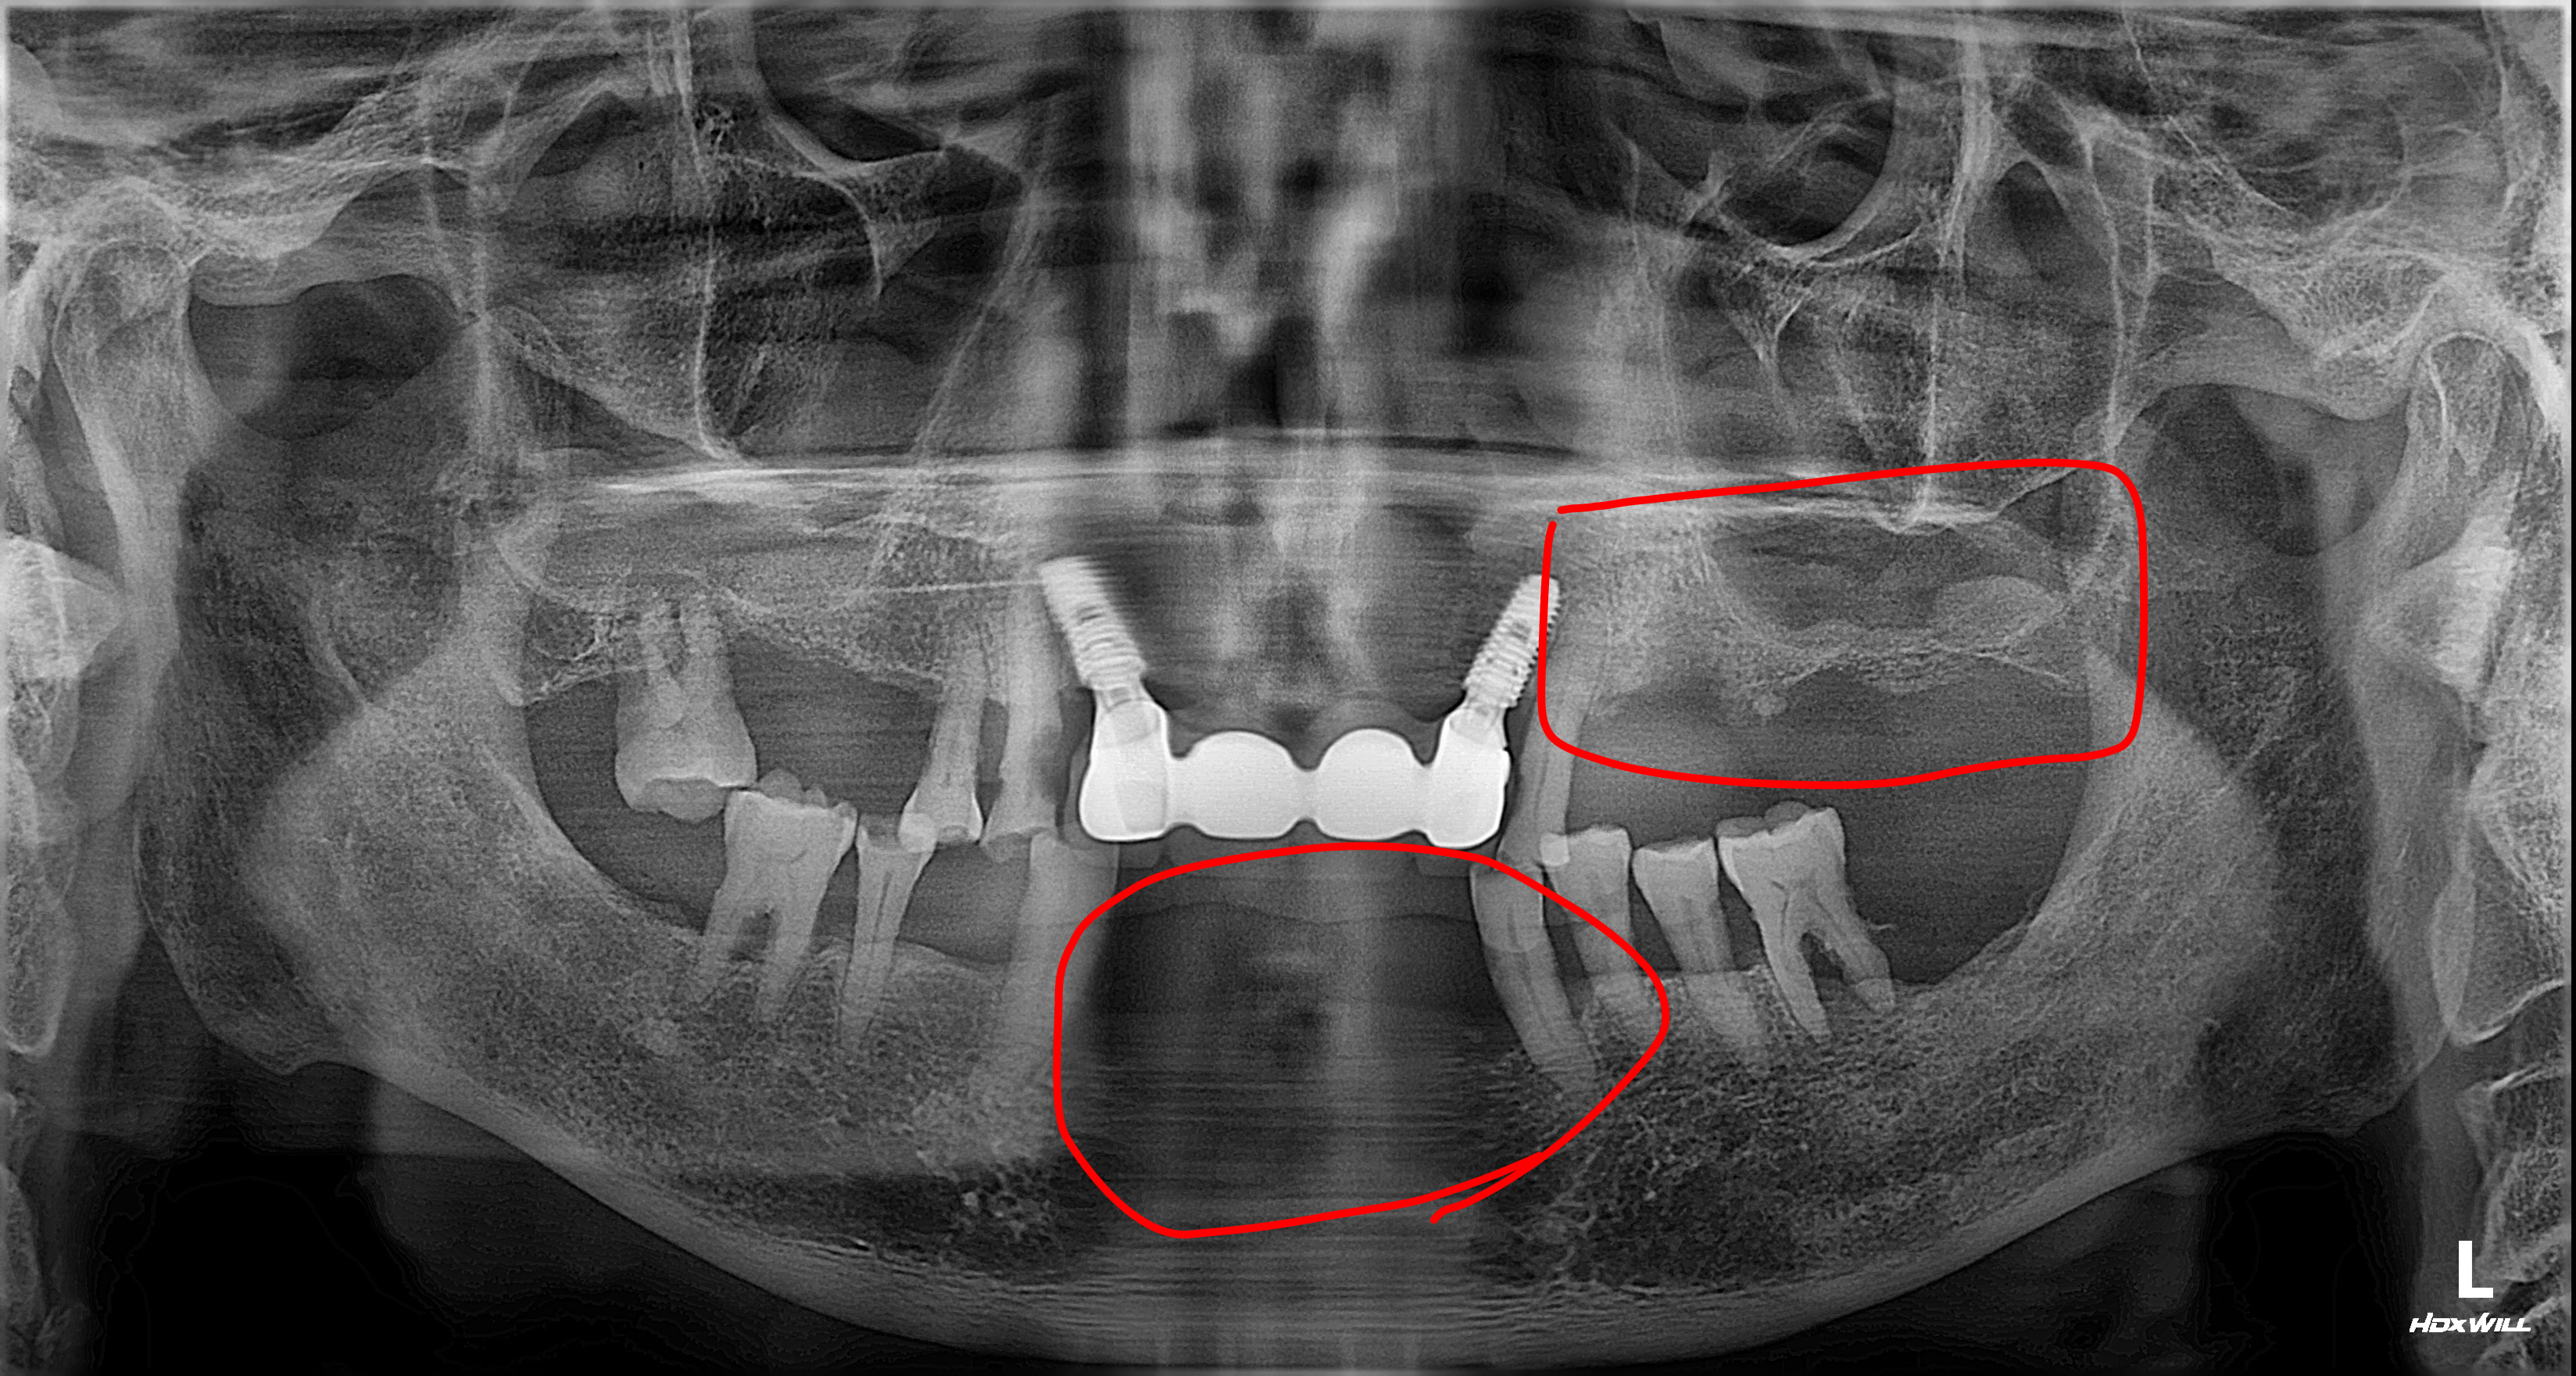

방사선 사진에서 확인할 수 있듯, 좌측 상악 어금니 부위는 치아가 빠진 지 오래되어 잔존 치조골(잇몸뼈)이 매우 얇아진 상태였습니다. 임플란트를 단단하게 고정할 뼈가 부족했기 때문에, 위턱뼈 속의 빈 공간인 상악동 막을 조심스럽게 들어 올리고 그 공간에 뼈를 채워 넣는 '상악동 거상술'을 시행했습니다.

수술의 효율성을 높이고 환자분의 내원 횟수를 줄이기 위해 상악동 거상술과 임플란트 픽스처 식립을 동시에 진행했습니다.